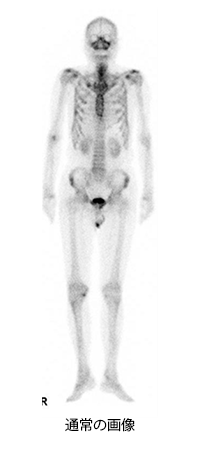

全身の骨の状態を見る検査です。この検査は、午前中に検査用の薬を注射します。撮像は午後行います。撮像時間は約30分です。使用する薬は、主に尿中に排泄されるため、尿がたまっていると膀胱周辺の骨の情報がわかりにくくなります。そのため、撮影直前にお手洗いに行っていただきます。